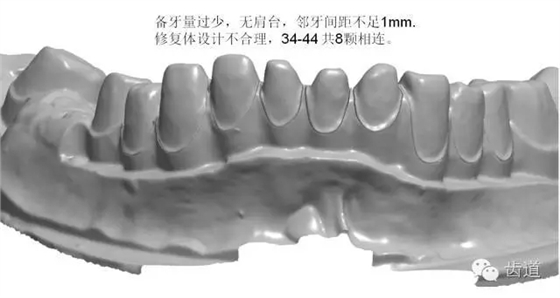

如:無(wú)肩臺(tái)、凹面肩臺(tái)、邊緣線不清晰、雙重邊緣線、備牙空間不足、基牙有倒凹或牙橋沒(méi)有共同就位道、基牙切端或頜緣過(guò)于尖銳等等。

解決方案:按要求制備基牙 1.將基牙預(yù)備成圓緩的斜面肩或軸-頸線角圓鈍的水平直角肩臺(tái),建議制備肩臺(tái)寬度為0.5~1.0mm。 2.咬頜面和切端需磨除0.8~1.5mm,軸面聚合角度為3°~6°,軸壁與咬頜面的連接處應(yīng)圓鈍,轉(zhuǎn)角半徑大于0.5mm. 3.頜面120°~140°的開(kāi)放角度可以保證在切削過(guò)程中精確的復(fù)制出內(nèi)冠的表面,進(jìn)而達(dá)到完好的密合。 4.連橋制備時(shí)要求基牙間具有共同就位道,避免倒凹。